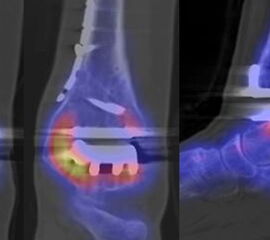

Abbildung 8.8.a bis d: Patientin mit bekanntem Knick-Senk-Fuß. Anamnestisch Schmerzen in beiden Füßen, links > rechts seit ca. 2 Jahren. Fragestellung: Status der bekannten Fußwurzelarthrosen vor geplanter OP. Neben, unter anderem fortgeschrittenen Arthrosen im Naviculo-Cuneiforme-Gelenk, Nachweis einer Tibialis posterior-Sehnen-Tendinitis mit begleitender Periostitis/Ostitis am Malleolus postero-medial. Abbildung 8.8.a und b: in der Frühphase (2 Minuten nach Tracerinjektion) sind lineare Anreicherung des Tracers im Verlauf der linken Tibialis posterior Sehne zu sehen.  In der  Mineralisationsphase im SPECT/CT begleitende Periostitis/Ostitis am Malleolus postero-medial. Abbildung 8.8.c und d: Der Blick auf das CT im Weichteilfenster offenbart diffuse entzündliche Verdickungen im Verlauf der linken Tibialis posterior Sehne. Rechts unauffälliger Befund. Unten beispielhaft die schmerzhafte NC-Arthrose.

Abbildung 8.9. a bis c: Extern MRT-morphologisch V. a. Coalitio calcaneo-naviculare. Anamnestisch Schmerzen im linken OSG seit ca. 1,5 Jahren, gehäuftes „Umknicken“ des linken Fußes, Pes planus bds.. Abbildung 8.9.a zeigt die 3D-Früh-SPECT aus verschiedenen Blickwinkeln. Wie in Abbildung 8.8.a findet sich hier eine deutliche lineare Tracerakkumulation im Verlauf der linken Tibialis posterior Sehne. Abbildung 8.9.b: In der Mineralisationsphase wie auch im vorhergehenden Fall ossäre Reaktion postero-medial am Mallelolus medialis als Zeichen einer chronischen Tendinitis. Die Durchsicht der 7 Wochen zuvor angefertigten externen MRT bestätigte den Befund (er war leider nicht beschrieben worden). Im SPECT/CT wurde eine Coalitio ausgeschlossen.

Abbildung 8.10.a bis e: Patient mit Verdacht auf symptomatisches Os peronaeum. In der Früh-SPECT/CT eindeutiger Nachweis einer ausgeprägten Tendinitis der Peronealsehnen links. In der Mineralisationsphase Stessreaktion im Bereich eines mehrgeteilten Os peroneaum links und lateral Calcaneus.